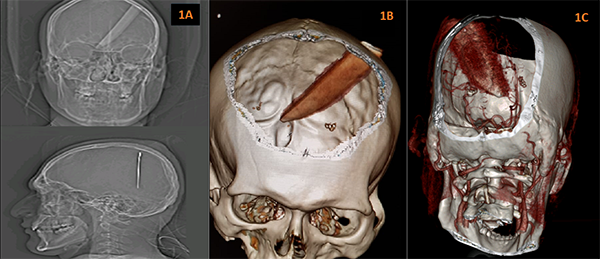

Paciente permanece hospitalizado por 12 días: 3 días en unidad de cuidados intensivos, es extubado a las 48 horas y 9 días en piso de neurocirugía. TC simple de cráneo a las 24 y 48 horas postquirúrgicas evidencian hemorragia intraparenquimatosa en lecho quirúrgico, zona de edema perilesional y neumoencéfalo (Figuras 2A - C). Neurológicamente presenta parafasia, dislalia, hemiparesia derecha FM 4/5, disociación izquierda derecha y disminución de la agudeza visual bilateral, por lo que es valorado por oftalmología con fondo de ojo normal, descartando patología ocular.

Paciente es dado de alta con mejoría de sintomatología neurológica antes descrita, Glasgow 15/15 y dismetría leve. Se realiza TC de control al mes postquirúrgico evidenciándose hemorragia intraparenquimatosa residual menor a 30cc, que no ocasiona sintomatología neurológica importante, además de no generar efecto de masa ni desplazamiento de estructuras por lo cual no se adopta conducta quirúrgica (Figuras 2D y 2F).

Figuras 2: A-C:

TC Simple de Cráneo 24 Horas Postquirúrgicas: A) Corte axial: Hematoma intraparenquimatoso (78UF) parietoccipital izquierdo de 3x2 cm, que colapsa la asta posterior del ventrículo lateral. B) Corte Coronal: Hematoma (80UF) 6,8x2,99 cm, más zona de craneotomía parietal izquierda. C) Corte Sagital: Hematoma 5,3X3,7cm (91UF) más edema perifocal. D- F) TC Simple de Cráneo Control al Mes Postquirúrgico: D) Corte axial: Hematoma residual intraparenquimatoso (51UF) parietoccipital izquierdo de 1,6x1,7 cm, con disminución del edema perilesional. E) Corte Coronal: Hematoma (66UF) 3,95x1,14cm. F) Corte Sagital: Hematoma 1,34X33,01cm (62UF).